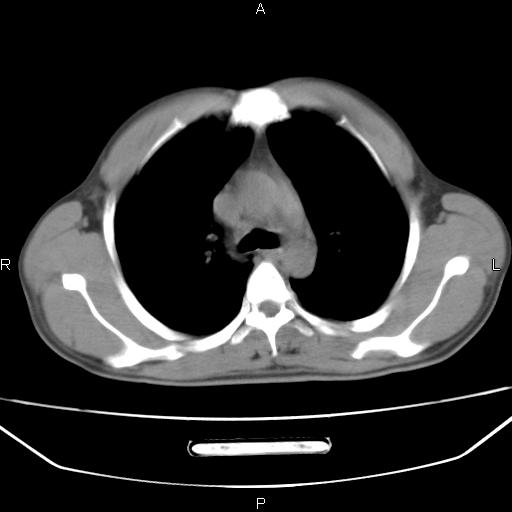

左下肺片状高密度影,境界模糊,密度不均,考虑感染性病变可能性大,建议抗炎治疗后复查。左肺门增大,不除外占位性病变,必要时支气管镜检。

建议强化或纤支镜观察,考虑肿瘤性病变可能性大